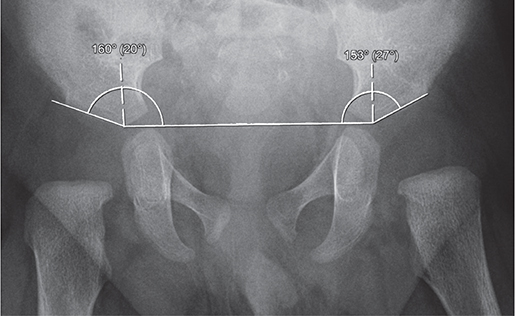

At Skåne University Hospital, children with a dislocated hip or a hip that can be dislocated are referred to a pediatric orthopedic surgeon who initiates treatment [6,7]. Children with suspected hip instability are treated if > 25% of the femoral head can be subluxated, as assessed with dynamic ultrasound [8]. Treatment with the von Rosen splint was initiated within 2 weeks from birth in all children. The splint was worn day and night, and parents were informed not to remove it. All patients had weekly checkups and were bathed by nurses at our outpatient clinic. There was no difference in treatment between Barlow- or Ortolani-positive hips. We have shown that acetabular index (AI) at 12 months age does not differ between hips treated for 6 compared with 12 weeks [5]. AI at 3 and 12 months was measured on pelvic AP radiographs according to Tönnis (Figure 1) [9], and subgroup analysis of pathological and healthy hips was performed. The study is reported according to STROBE guidelines.

Figure 1. Acebatular index calculated at 3 months of age (20° right, 27° left). It is measured by drawing a horizontal line (Hilgenreiner) between the inferior portion of the iliac bones at the triradiate cartilages and measuring the angle formed between this line and a second line along the lateral acetabular roof.